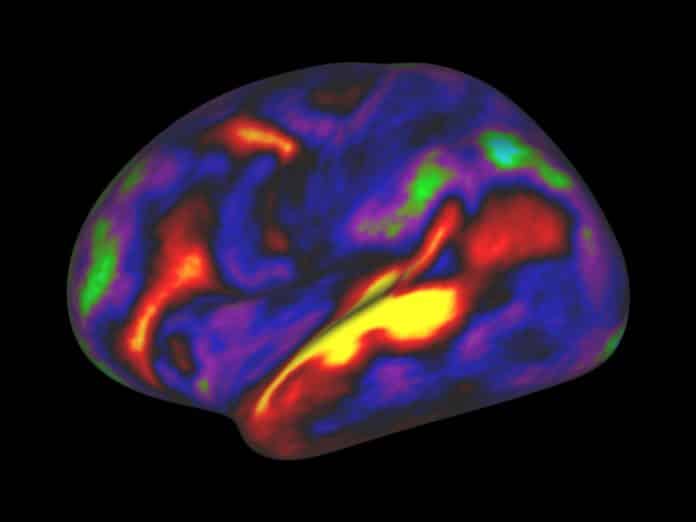

Around day 5 after transplantation, blood vessels in the organoids could be detected using a fluorescent dye, and by day 14 an extensive network of vessels had grown deep within the human tissue graft.

Within two to 12 weeks, the organoids were sprouting additional neurons, including ones found in very specific regions of the human cortex; glia cells including astrocytes; and neural stem cells. By 14 days almost all the organoids had developed a rich network of blood vessels carrying nutrients and oxygen, allowing them to survive for up to 233 days. Their structure and cell maturation was that of a newborn.

The implanted organoids were also sending axons — the biological wires that carry brain signals from one neuron to another — into both sides of the mouse brain, not only the side with the window, and forming such strong synapses with mouse neurons that the neural activity of the two species was synchronized.